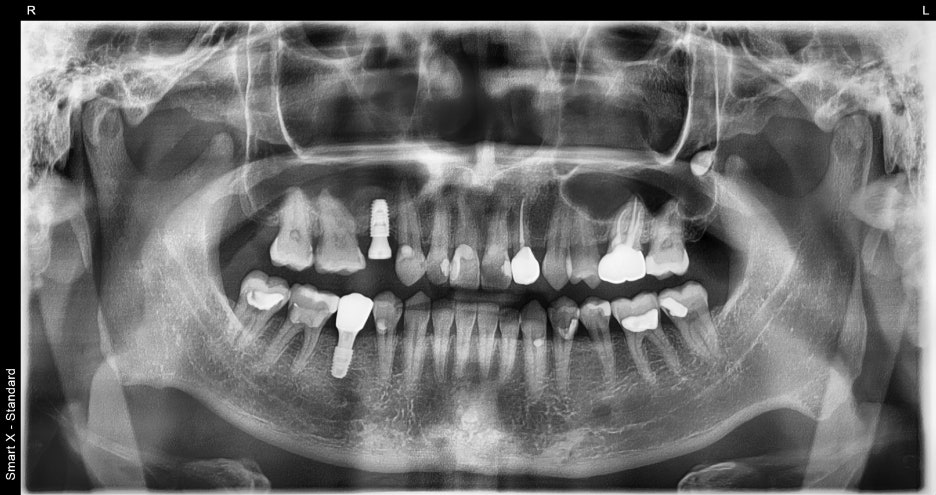

Panoramic imaging showed that the lower right molar had fractured

and could not be preserved.

It was diagnosed as a case in which immediate implant placement after extraction was possible.

The upper right premolar had been missing for a long time,

but because the degree of bone resorption in the jawbone was not severe,

implant treatment was possible without additional bone grafting.

1st visit: #45 extraction + immediate implant,

#15 implant placed simultaneously